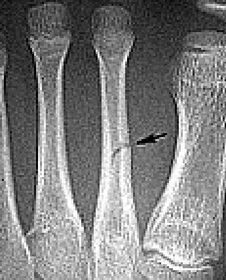

| What do the arrows show? | Stress fracture |

| Describe what has happened at the shaft of the 3rd met | Exuberant periosteal new bone production. May have resulted if a stress fracture was not treated and the patient continued weight bearing activities. |